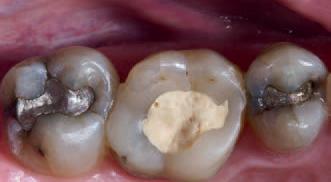

Procedure and treatment

Using local anaesthetic and rubber dam isolation, access was obtained through the composite resin restoration. While the cracks were visible, they appeared similar to the image from 2018 (Fig. 4). The roof of the pulp chamber was removed and vital tissue was found, which did not appear to be heavily inflamed (Fig. 5). A pulp stone was also present (Fig. 6). Removing this revealed bleeding pulp tissue at the opening of the root canals. A cotton pellet soaked in NaOCl was placed on the pulp tissue at the opening of the root canal and after five minutes the bleeding had ceased (Figs. 7 and 8).

Fig. 5: Initial exposure of the pulp chamber showing slight bleeding and pulp stone.

Fig. 6: Pulp stone removed.

Fig. 8: Palatal root opening with vital tissue after bleeding has stopped.

Fig. 7: Buccal root openings with vital tissue after bleeding has stopped.